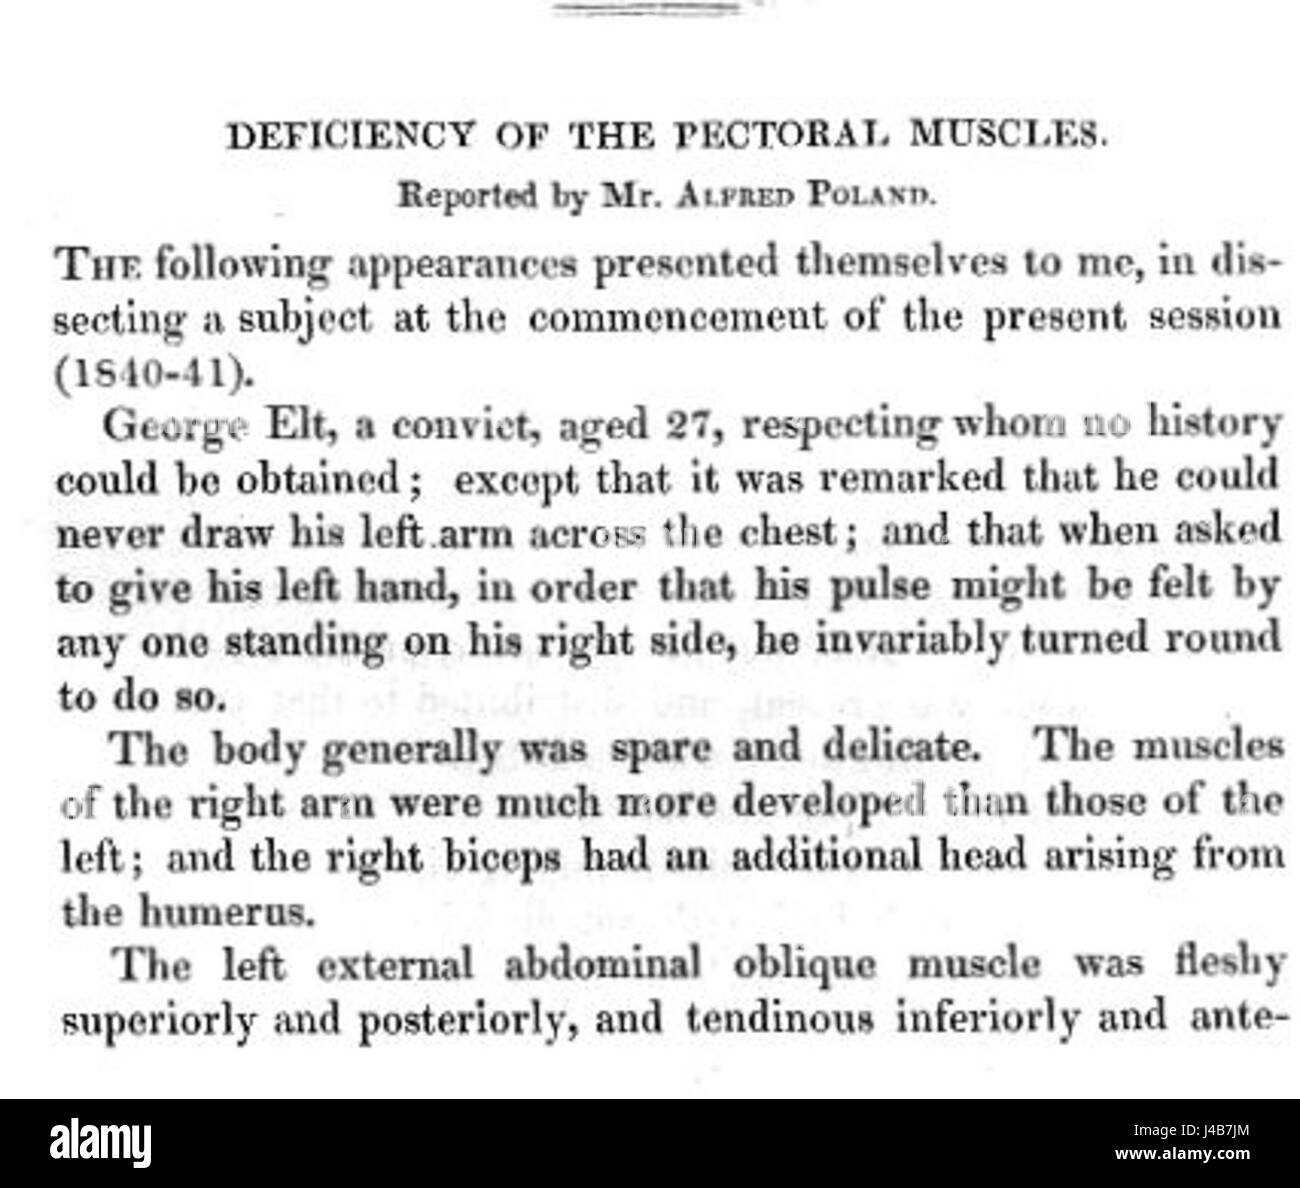

Poland Syndrome Description Stock Photo - Alamy

www.alamy.comPoland Syndrome | Radiology Reference Article | Radiopaedia.org

www.alamy.comPoland Syndrome | Radiology Reference Article | Radiopaedia.org

Poland syndrome description stock photo. Healthjade anomaly. Living with poland syndrome. how to live with poland syndrome?